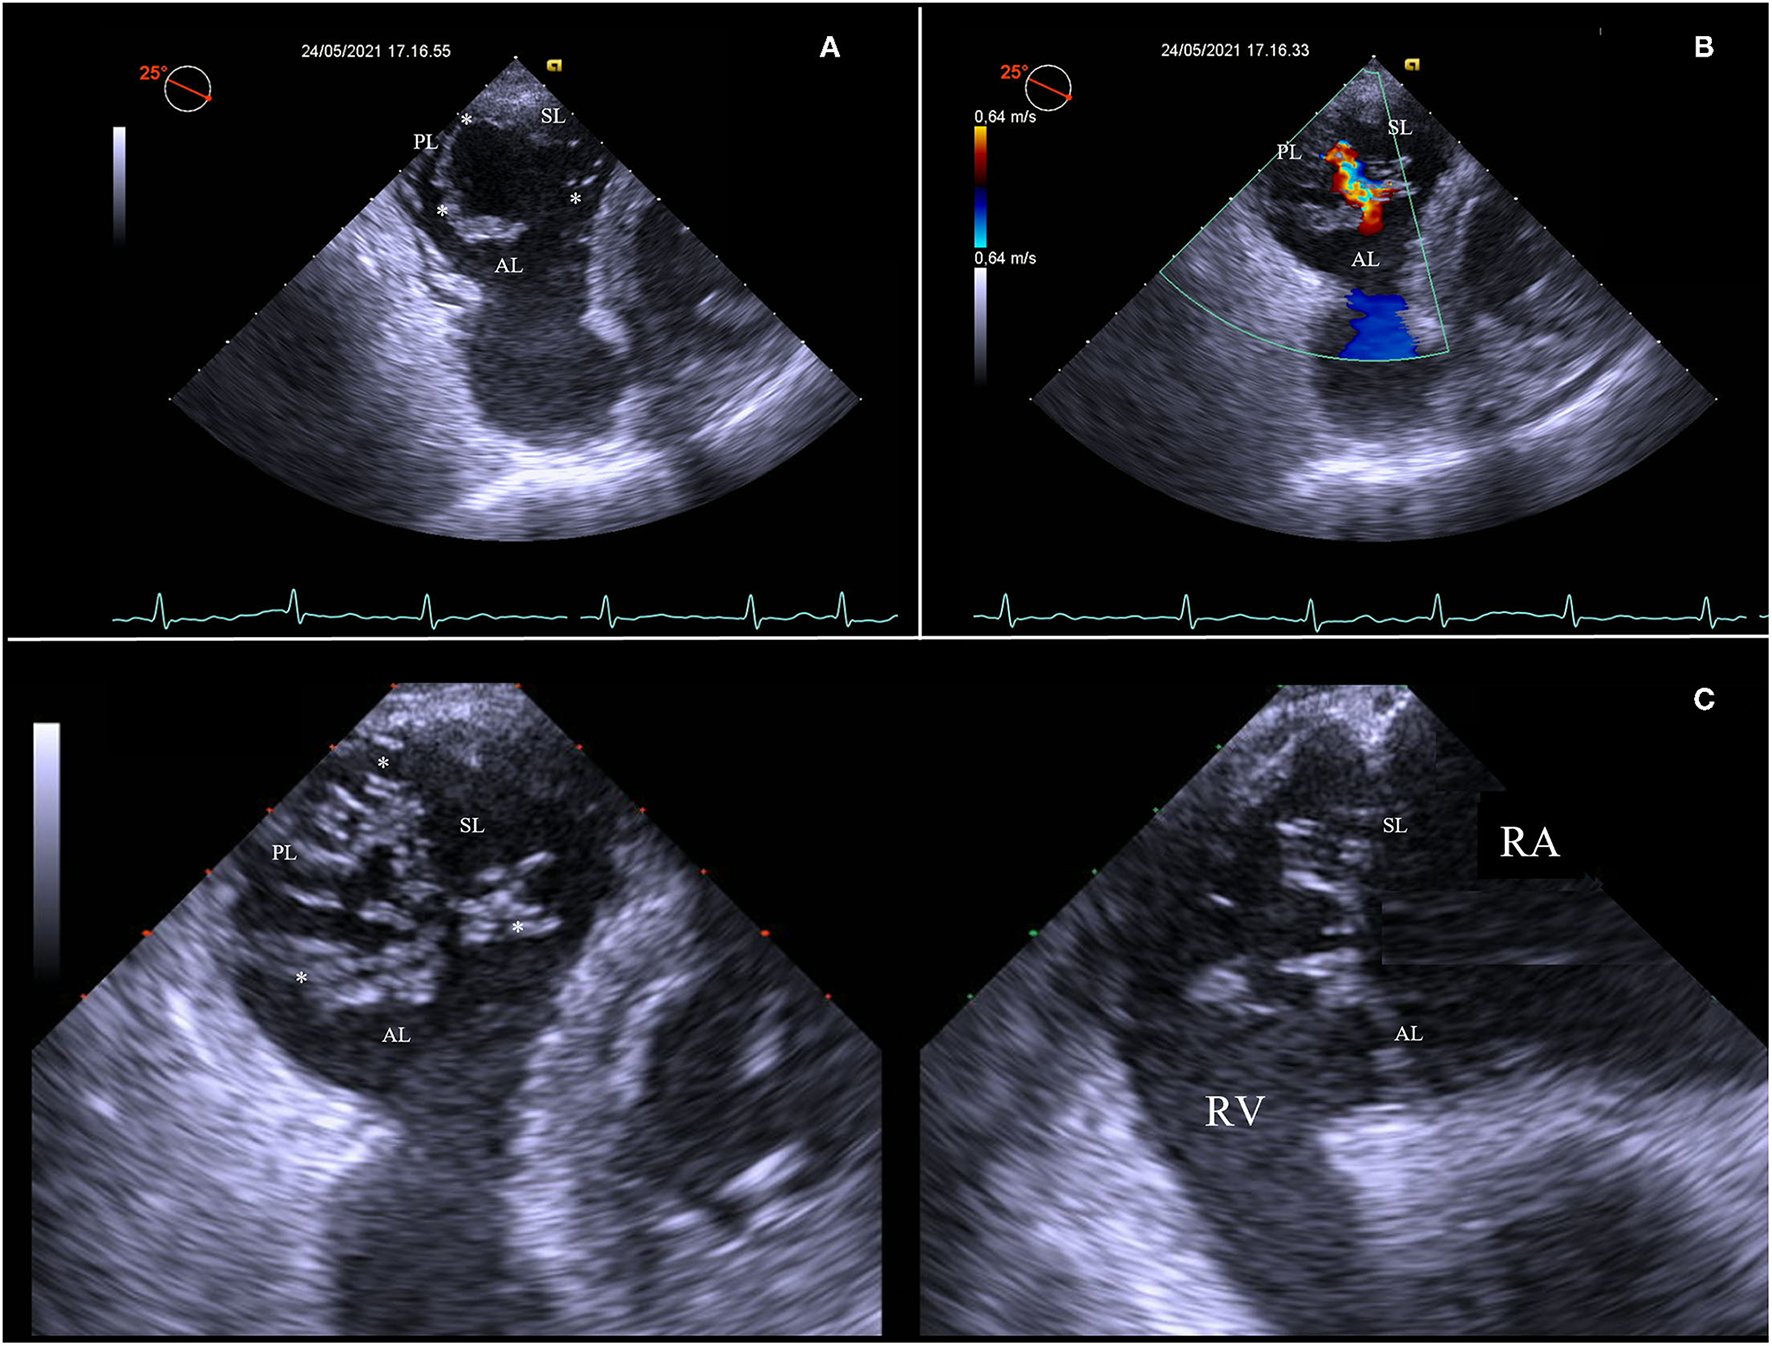

Then, advancing the TEE probe into the stomach results in transgastric views, which enables to obtain optimal view settings to (Figure 2):

Figure 2

Short-axis transgastric view, identifying all three leaflets and commissures (asterisks) (A), as well as the origin and distribution of the regurgitation jet along all the rim of coaptation (B). Transgastric biplane view focusing on tips of leaflets (C). AL, anterior leaflet; PL, posterior leaflet; RA, right atrium; RV, right ventricle; SL, septal leaflet.

Identify all tricuspid leaflets and commissures. The transgastric short-axis view is the only 2D view that can simultaneously visualize all three TV leaflets;

Visualize zones of coaptation and all coaptation gaps;

Analyze the distribution of the TV regurgitation;

Align the view parallel to the annulus of the TV and focus on the leaflets tips at closure, using the biplane modality.